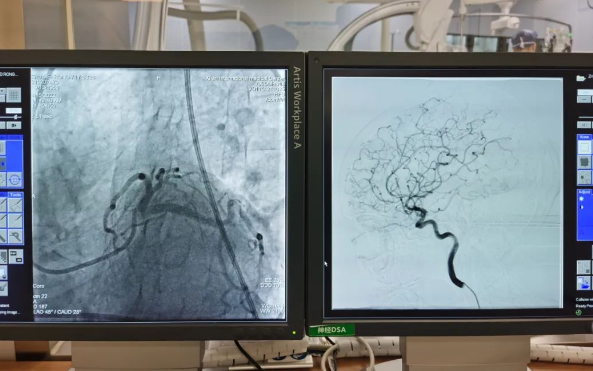

術(shù)前準(zhǔn)備就緒后,心內(nèi)二病區(qū)曾廣偉主任、高釗副主任醫(yī)師、神外科陸丹副主任醫(yī)師共同為患者行腦血管造影術(shù) 冠狀造影術(shù)。術(shù)后,朱奶奶恢復(fù)良好。

陸丹副主任醫(yī)師介紹,由于腦血管疾病和心血管疾病有著共同的病理變化基礎(chǔ)——?jiǎng)用}粥樣硬化,臨床中,兩類(lèi)疾病交叉存在的情況十分多見(jiàn)。“心腦同治”的模式不僅能讓患者獲得較好治療,還能夠降低患者就醫(yī)的時(shí)間成本和經(jīng)濟(jì)成本。